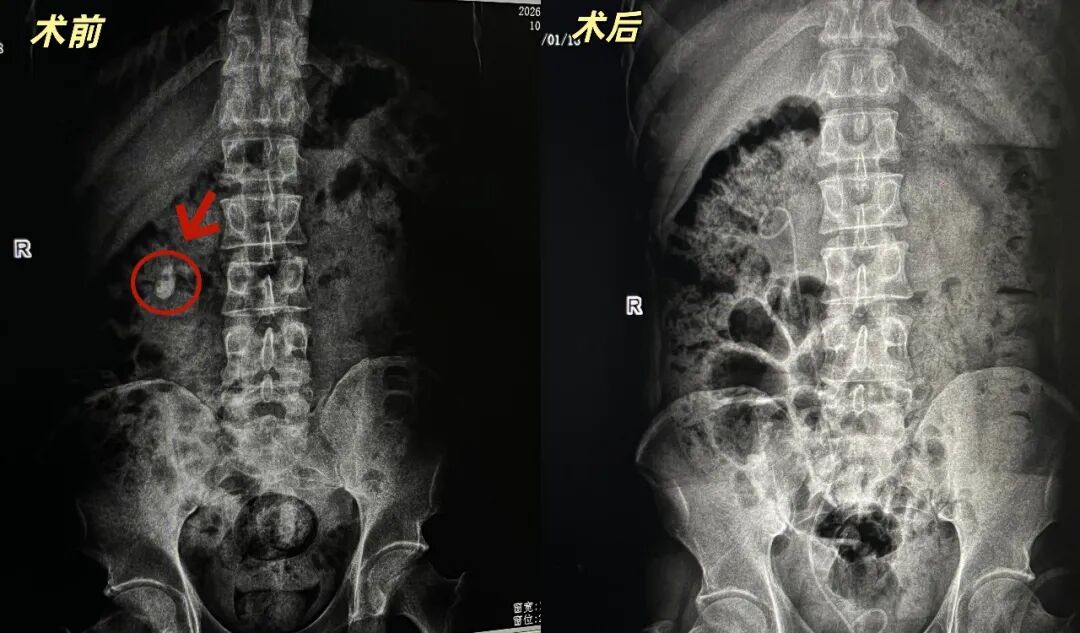

图片

在与患者及家属进行充分沟通,并获得手术同意后,医疗团队为患者实施了“经皮肾镜下右肾结石碎石取石术+经尿道输尿管支架管置入术”。术中,医生顺利穿刺、碎石,成功清除了困扰患者的结石;麻醉医生全程严密监护,确保生命体征平稳;护理团队默契配合,为手术的顺利进行提供了坚实保障。

术前

术后